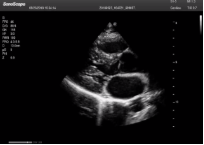

不同的探頭對應(yīng)于不同的臨床領(lǐng)域,不同的探頭頻率也應(yīng)用于不同的人體組織。超聲波在人體中的衰減與探頭頻率有關(guān),探頭頻率越高,穿透力越弱,分辨率越高,而探頭頻率越低,穿透力越強,分辨率越低。因此在檢查淺表器官時應(yīng)選用高頻探頭,而檢查深部臟器時則選用穿透性強的低頻探頭。